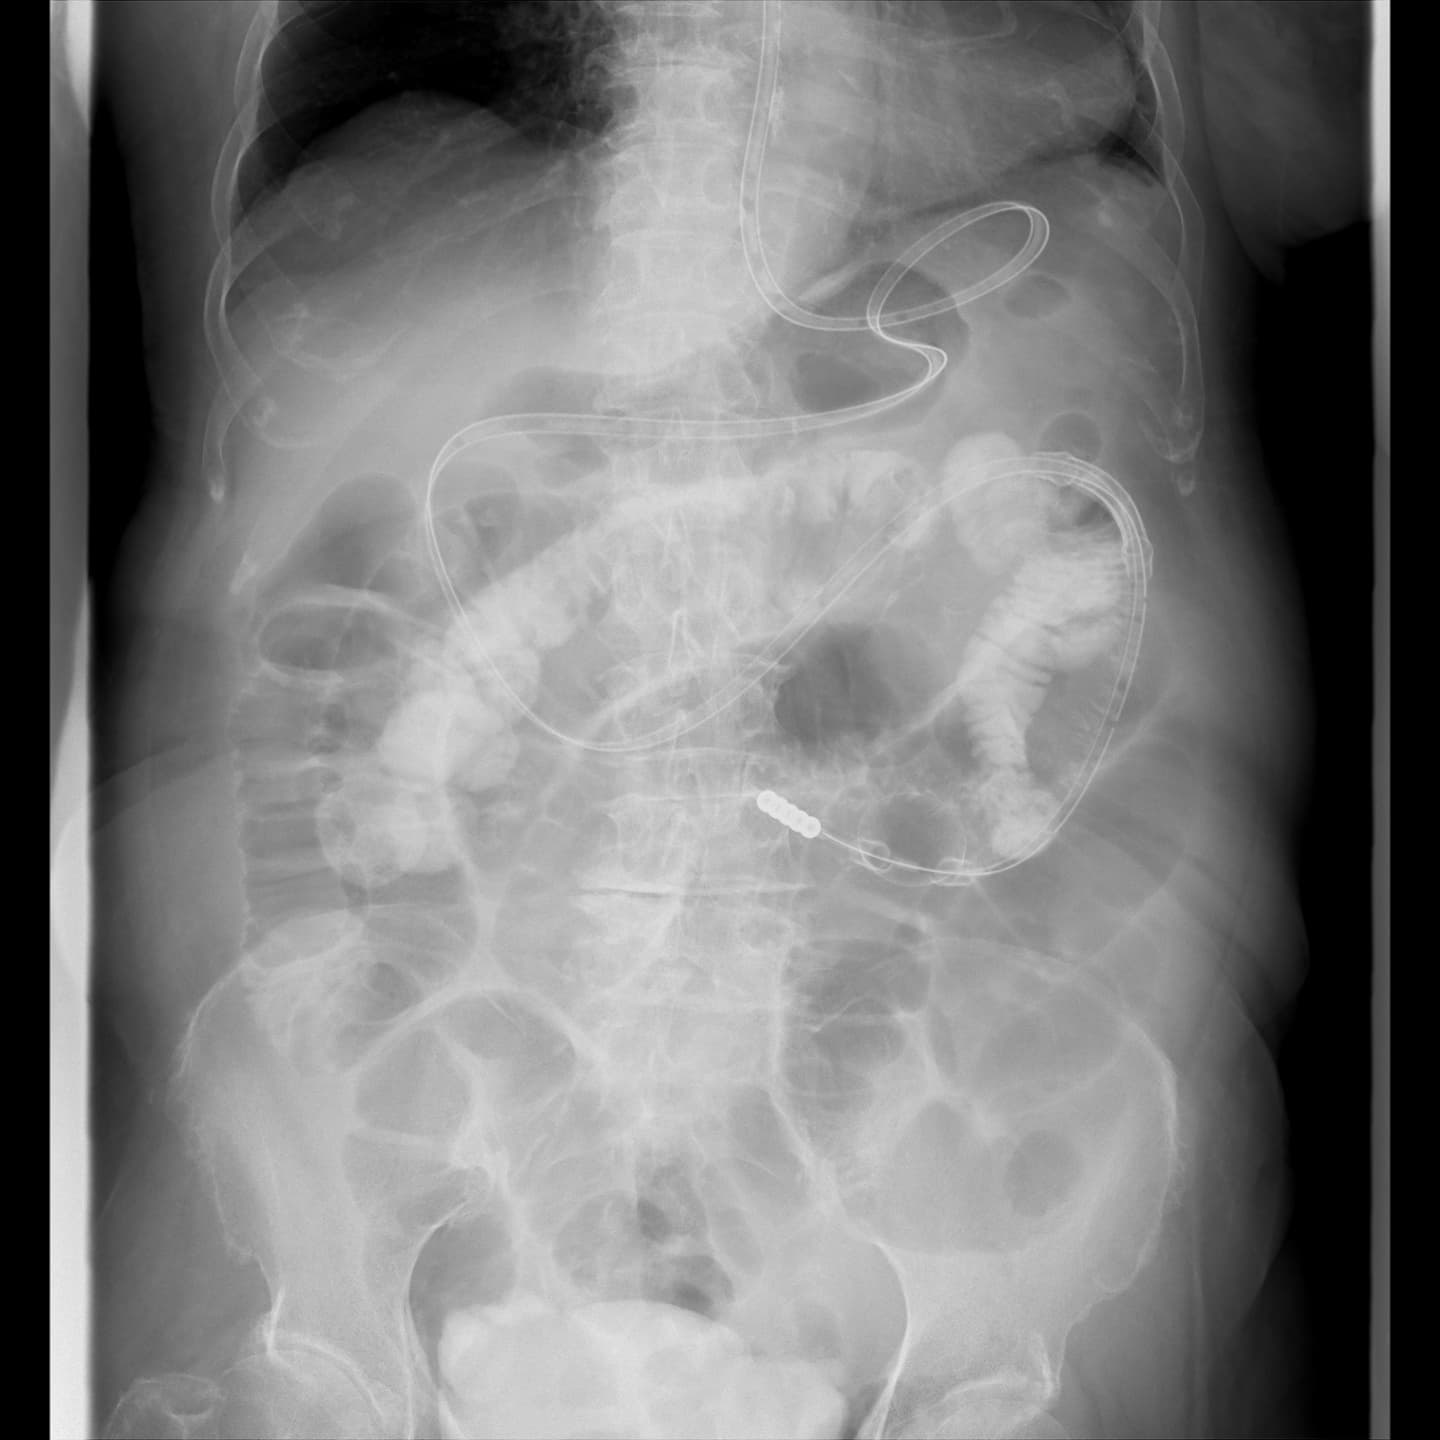

消化器では、バリウムなどの造影剤を使用して、上部消化管(食道・胃・十二指腸など)や下部消化管(大腸など)の造影検査を術前精密検査や術後検査として行います。

術後のドレーン管理や、超音波装置を併用したPTCD(経皮経肝胆道ドレナージ)やPTGBD(経皮経肝胆嚢ドレナージ)などの治療も行っています。

消化器の検査も透視検査室5と併用しながら日々検査が行われています。